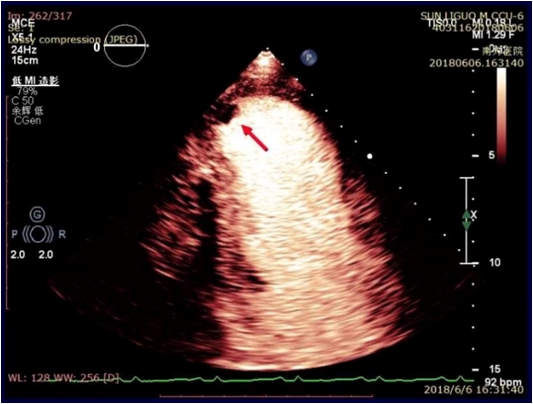

左心心尖室壁瘤形成,心尖附壁血栓,LVEF 39%